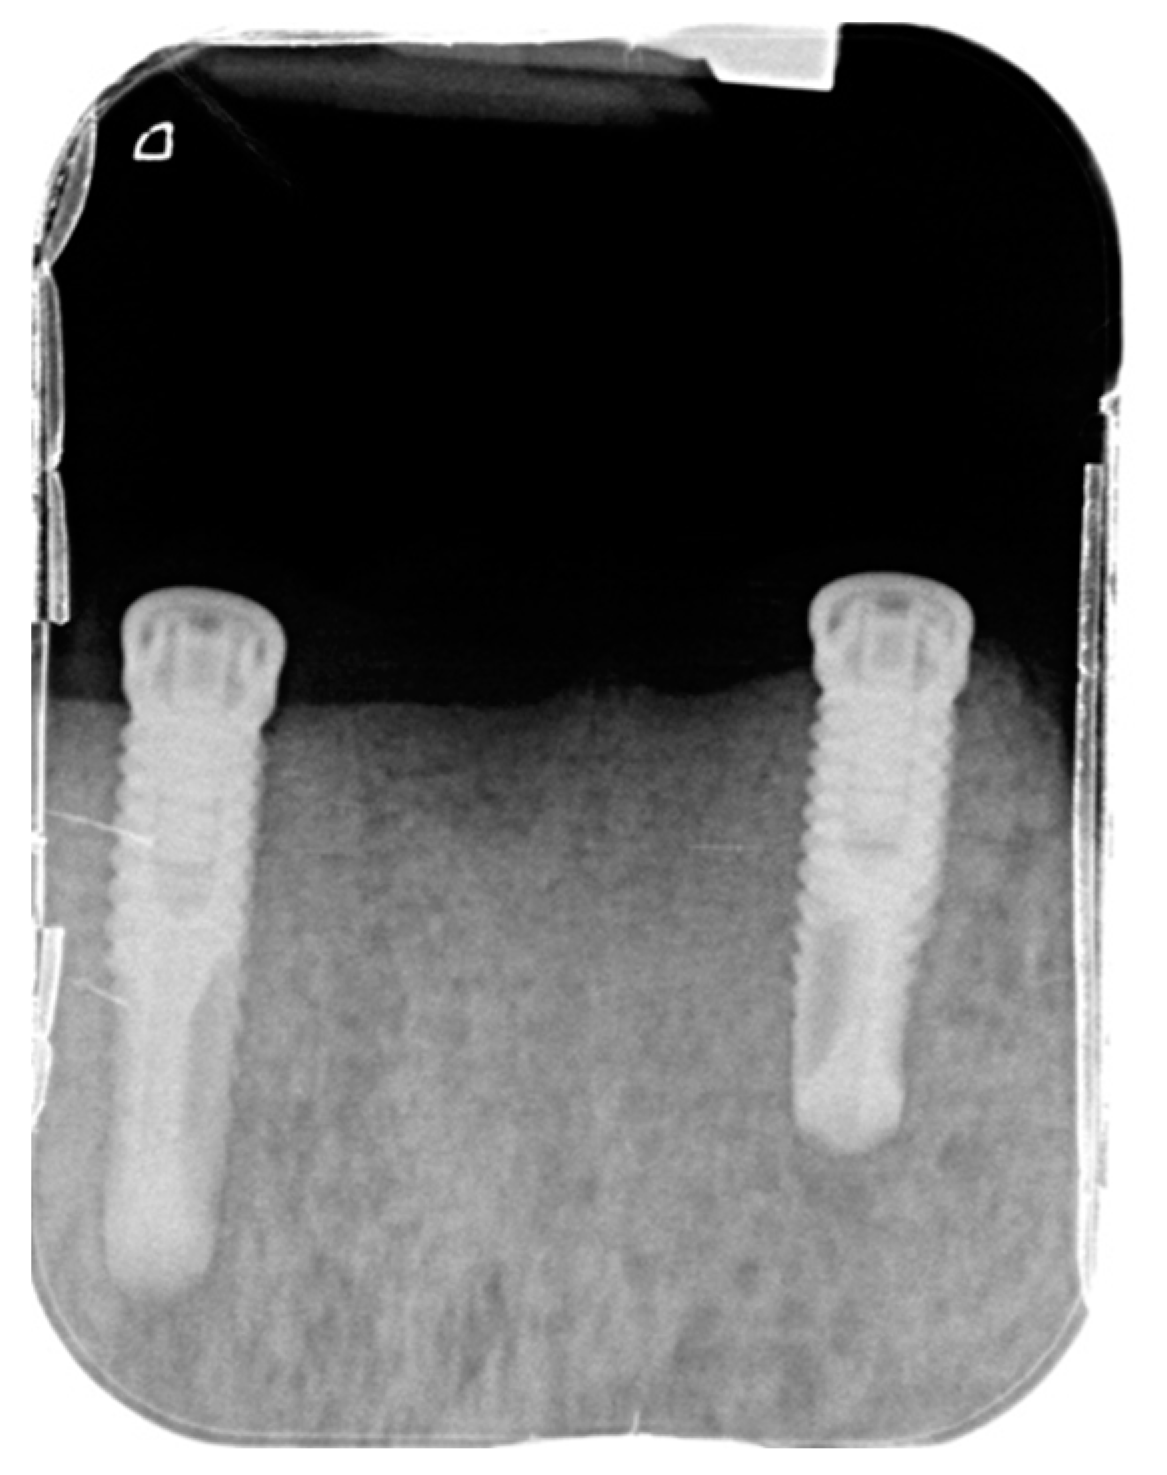

- surgical insertion of two anterior implants in the region of the mandibular canines

- rehabilitation with implant-supported OVD adapting the current complete removable denture, 3 months after implant surgery.

2.1.3. Follow Ups and Implants Insertion

3.1. Case Report